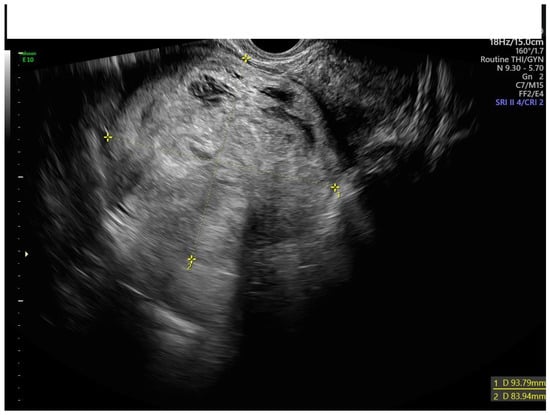

2.3. Ultrasound Assessment